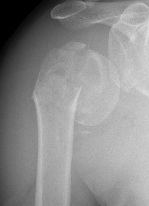

- displaced proximal humerus fractures

Displaced 2 part SNOH fractures in young patient